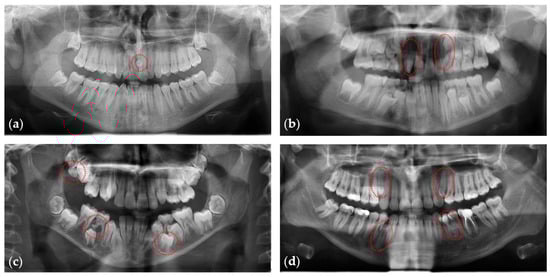

Further evaluation of the anonymized radiographs was performed by two researchers (E.H, L.F.) to verify the data extraction procedure. All panoramic radiographs were viewed on a screen to identify tooth patterns. For this purpose, hard copy (analogical) radiographs were scanned using an Epson Perfection V700 scanner with a resolution of 600 dpi at a scale of 1:1 and saved in .tiff (tagged image file format) format (Figure 1). Both researchers re-assessed the data extraction procedure of the entire sample one month after the first assessment, and any disagreements were resolved through consensus and consultation with the last author. All data were recorded in an Excel spreadsheet.

Figure 1.

Panoramic radiographs showing individuals with (a) one, (b) two, (c) three, or (d) four supernumerary teeth, indicated by dashed red circles.